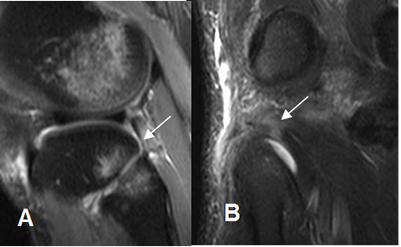

Fig 127. Lesión de la esquina posterolateral

A: RM sagital en STIR. Contusión del compartimiento lateral, con cambios inflamatorios que rodean el ligamento popliteofibular, el cual está adelgazado.

B: RM coronal en STIR. Cambios inflamatorios con área hiperintensa en el tendón poplíteo, por lesión muscular GI-II.